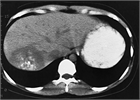

1. エキノコックス症の画像診断において、MRIによる小嚢胞性病変の確認が有用である(推奨度2)